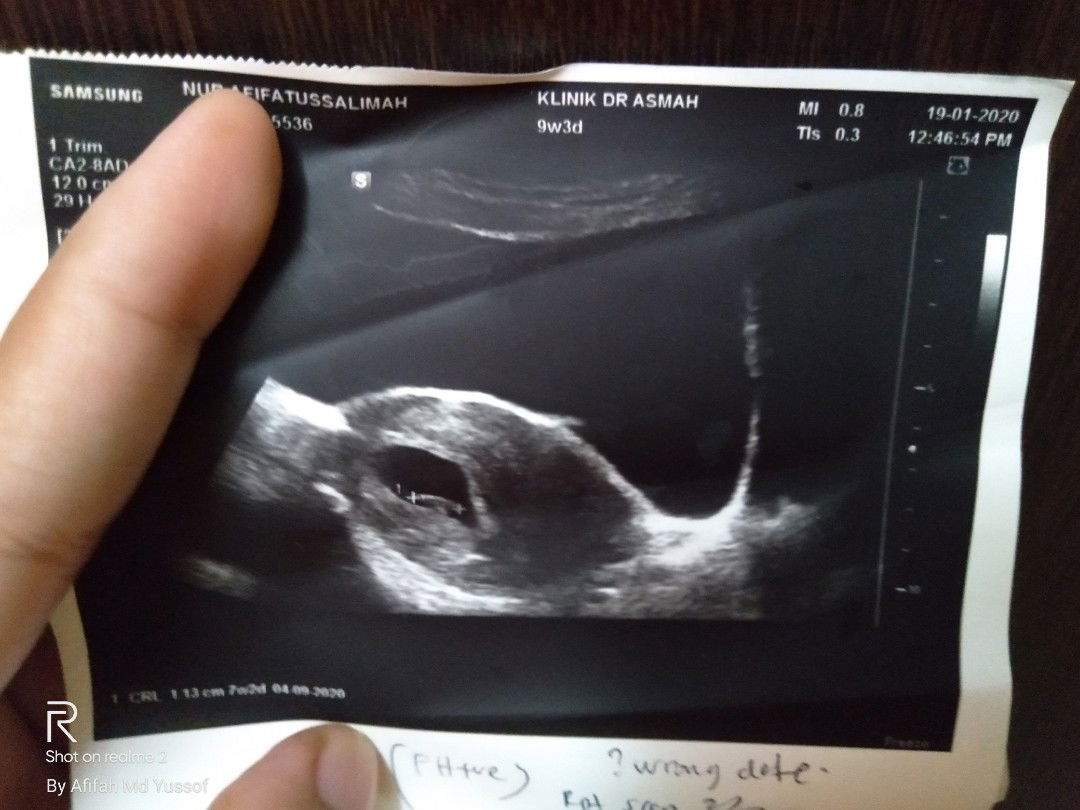

scan berbeza duedate dari lmp

Saya dah repeat scan baru ni (9w 3d) untuk anggaran usia kandungan dan due date.Tapi hasil scan baby dah nampak elok dengan jantung.Cuma usia berbeza jadi 7w 2d.. Doktor suruh repeat untuk konfirm redd.Ada mummy² pernah alami mcmni x?lepas scan balik lagi 2w beza banyak x due?